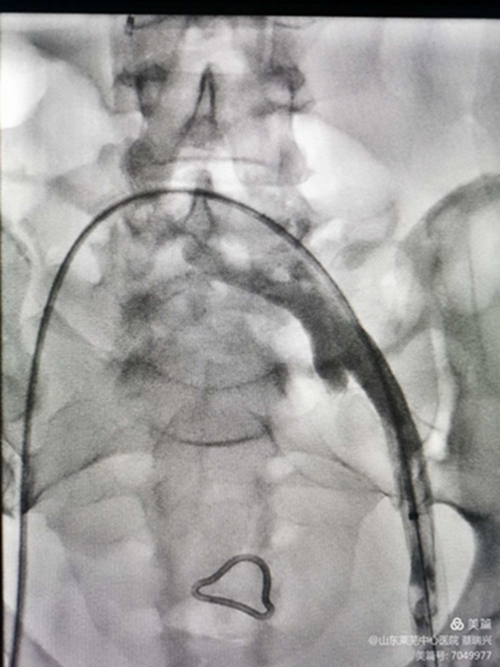

女性,55歲,左下肢腫脹2天入院,疼痛,無明顯功能障礙。左下肢I(xiàn)I度水腫,脹力高。彩超示,左下肢股淺靜脈、股總靜脈、髂外靜脈血流不暢,見有血栓,呈低回聲。髂總靜脈觀察不清。肺動(dòng)脈CTA示無栓塞。取右股靜脈入路,造影證實(shí)左髂總靜脈閉塞,開通后,左下肢深靜脈造影示左下肢股淺靜脈、股總靜脈、髂外靜脈均有充盈缺損,留置溶栓導(dǎo)管6天。今天給予左髂總靜脈支架成形術(shù)。如圖,溶栓導(dǎo)管造影證實(shí),左髂總?cè)杂兄囟泉M窄,血流不暢,易再閉。

與右髂總匯合處,重度狹窄。

取出濾器,預(yù)行左髂總靜脈成形術(shù),但又閉塞,導(dǎo)管不能通過。